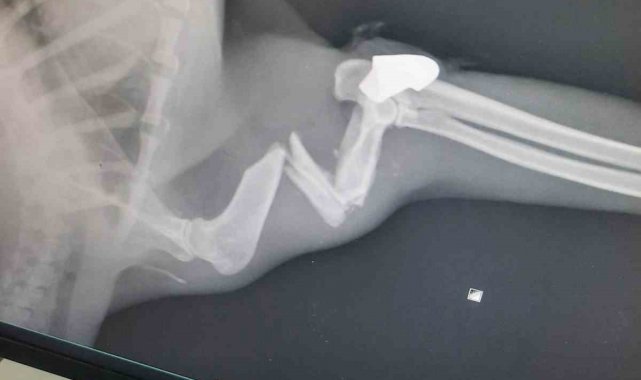

Zonguldak Belediyesi Veteriner Hizmetleri Müdürü Rıza Akçay ise kedinin durumu hakkında teknik bilgi verdi. Olayın "ateşli silah yaralanması" olduğunu belirten Akçay, "Röntgenlerini çektik, orada da belli. Sonuç olarak ameliyatını yaptık. Ameliyatı da başarılı geçti. Eski sağlığına inşallah kavuşacak. Yorgun mermi. Mermi çekirdeği de zaten üzerindeydi. Onun için diyoruz zaten yorgun mermi. Gerekeni yaptık" ifadelerini kullandı.